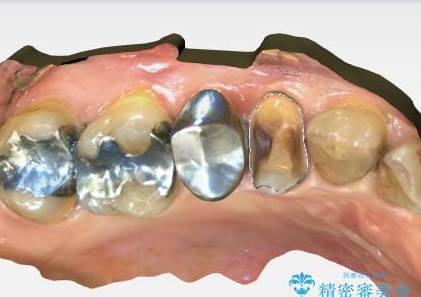

できるだけ歯質を残した1day治療 セラミックインレー

- 歯の詰め物が外れ、そのままにしていたのを治したいとのことで来院されました。残った歯質の量が少なく、できるだけ歯を残すために仮詰め期間の必要が無い1dayのセラミック治療を行いました。術後も経過良好です。処置においては虫歯も綺麗に除去しています。